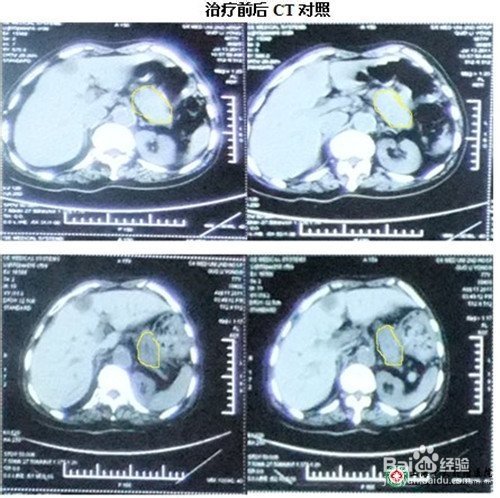

肝转移症状是导致胰腺癌预后较差的最主要原因之一,治疗起来也相对比较棘手。这时最重要的是患者在心态上要做好准备,通过积极有效治疗可在一定程度上改善患者生活质量。胰腺癌肝转移治疗,仅仅治疗肝转移病灶是不能取得预期的效果的,必须在此基础上同时治疗原发癌肿胰腺癌,才能取得较好的疗效。

胰腺癌肝转移治疗要根据肝脏转移性质以及胰腺癌患者的个体病情,选择以保守治疗为主的综合性、规范化、合理治疗,才能控制癌肿的进一步侵及,减轻病人临床痛苦,提高患者生活质量,使病人平安度过5年康复期尤为主要。

临床上手术治疗胰腺癌肝转移效果差,术后病人容易出现一系列并发症,很不利于患者的康复;放化疗、介入治疗可取得短时间疗效,但同时带给胰腺癌肝转移患者更多的烦恼,原因是由于这些局部疗法对癌细胞和人体正常细胞无辨别能力,在杀死癌细胞的同时也损害了人体大量正常组织细胞,强烈的毒副作用一般使患者难以耐受,还带来很大的肝肾毒性。